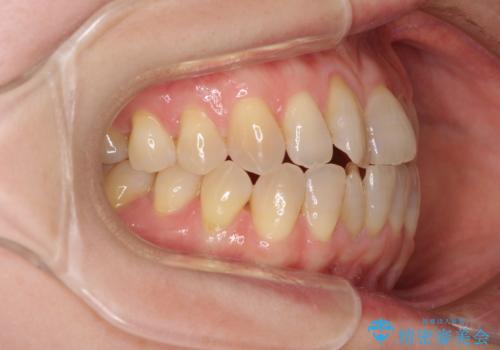

前歯の叢生と切端咬合 インビザラインによる矯正治療

上下前歯の先端同士が接触する切端咬合であったため、上顎は歯列を拡大し、下顎はIPR(歯と歯の間を削る)により叢生を解消しながら歯列を小さくすることとしました。

治療前から歯肉退縮が認められ、矯正治療により悪化する可能性が考えられたため、無理のない歯の移動と頻繁な経過観察を行いました。

切端咬合はスムーズに解消され、前歯の負担を軽減させることができました。